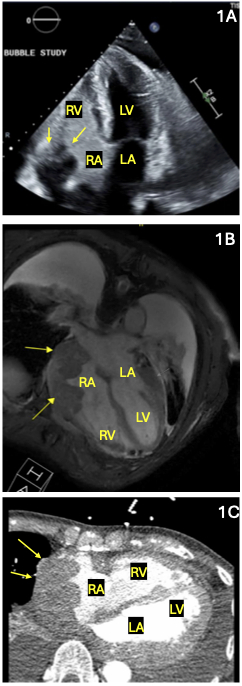

A 78-year-old male with past medical history of atrial fibrillation, hypertension, and recent admission for post-viral pericardial effusion status-post pericardiocentesis initially presented for a syncopal episode while climbing a flight of stairs. Transthoracic echocardiography (TTE) demonstrated marked asymmetric myocardial wall thickening involving the inferior, lateral, and posterior myocardial walls, concerning for an infiltrative process (Figure 1A). Cardiac magnetic resonance imaging (MRI) demonstrated 3.8cm thickening of the left ventricular (LV) and right atrial (RA) wall, consistent with an infiltrative malignancy (Figure 1B) that was again visualized on cardiac CT (Figure 1C). Positron emission tomography-computed tomography (PET-CT) revealed fluorodeoxyglucose (FDG) avidity in the right testis (2A), suspicious for possible testicular lymphoma or sarcoma, in addition to radiotracer uptake in the RA and LV (Figure 2B). The patient then underwent orchiectomy, from which pathology demonstrated diffuse large B-cell lymphoma (DLBCL) (Figure 3A-3C).